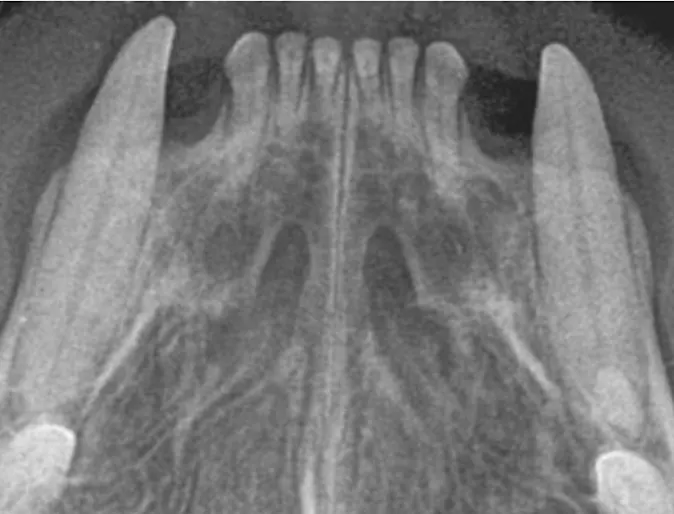

Before

Tartar and Periodontal Disease

After

Cleaning and necessary extractions